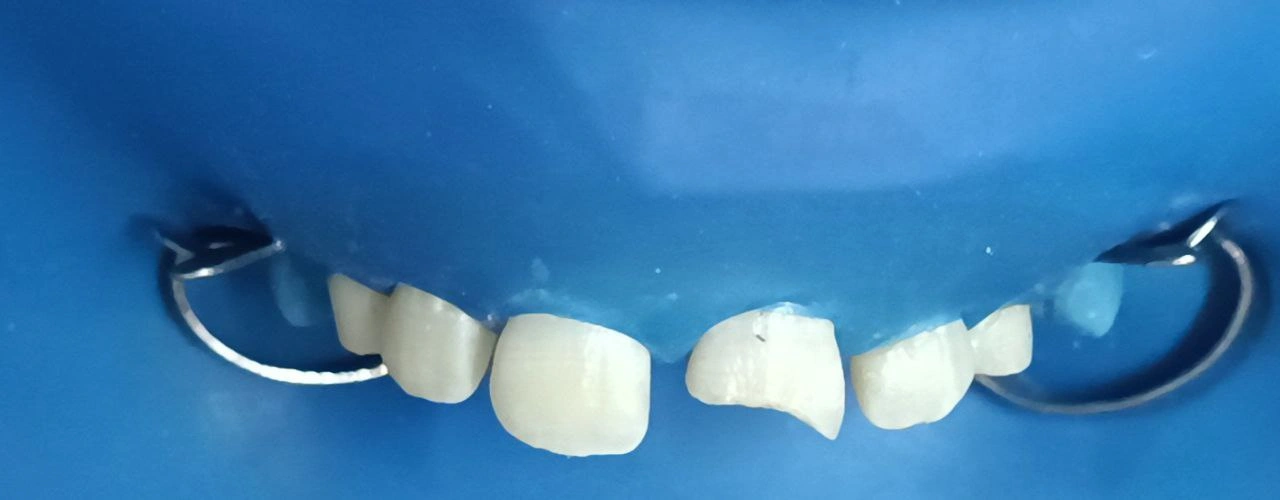

Clinical Cases